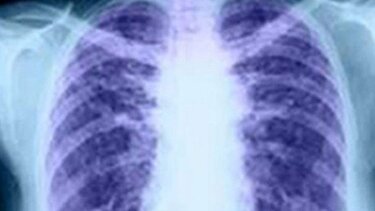

Περισσότεροι από 3,8 εκατομμύρια θάνατοι από καρκίνο του πνεύμονα αποφεύχθηκαν στις Ηνωμένες Πολιτείες Αμερικής κατά την περίοδο 1970-2022, λόγω της σημαντικής μείωσης του καπνίσματος που προήλθε από τον έλεγχο του καπνού. Αυτό διαπίστωσαν ερευνητές της Αμερικανικής Αντικαρκινικής Εταιρείας και η έρευνά τους δημοσιεύθηκε στο «CA: A Cancer Journal for Clinicians».

Τα αποτελέσματα της μελέτης έδειξαν ότι κατά την περίοδο αυτή αποτράπηκαν 3.856.240 θάνατοι από καρκίνο του πνεύμονα (2.246.610 σε άνδρες και 1.609.630 σε γυναίκες) και κερδήθηκαν περισσότερα από 76 εκατομμύρια ανθρωποέτη ζωής, με μέσο όρο 19,8 τα ανθρωποέτη ζωής κερδισμένα ανά θάνατο που αποτράπηκε.

Ο αριθμός των θανάτων από καρκίνο του πνεύμονα που αποτράπηκαν αντιπροσώπευε το 51,4% των εκτιμώμενων μειώσεων στους συνολικούς θανάτους από καρκίνο και ήταν σημαντικά μεγαλύτερος στους άνδρες (60,1%) από ό,τι στις γυναίκες (42,7%).

Ωστόσο, «παρά τα ευρήματα αυτά, ο καρκίνος του πνεύμονα εξακολουθεί να είναι η κύρια αιτία θανάτου από καρκίνο στις Ηνωμένες Πολιτείες και η νοσηρότητα και η θνησιμότητα από άλλους καρκίνους ή ασθένειες που αποδίδονται στο κάπνισμα παραμένουν υψηλές», σημειώνει ο Φαρχάντ Ισλάμι, επιστημονικός διευθυντής της έρευνας για τις ανισότητες στον καρκίνο στην Αμερικανική Αντικαρκινική Εταιρεία και επικεφαλής συγγραφέας της μελέτης. Ο ίδιος τονίζει ότι «χρειαζόμαστε μια ισχυρότερη δέσμευση σε τοπικό, πολιτειακό και ομοσπονδιακό επίπεδο για να βοηθήσουμε στην περαιτέρω μείωση του καπνίσματος και να αυξήσουμε σημαντικά την πρόοδο κατά της θνησιμότητας που σχετίζεται με το κάπνισμα. Είναι επίσης σημαντικό αυτά τα προγράμματα ελέγχου του καπνίσματος να σχεδιάζονται έτσι ώστε να απευθύνονται σε ομάδες με υψηλότερο κίνδυνο καπνίσματος, όπως άτομα με χαμηλότερο κοινωνικοοικονομικό επίπεδο, για να βοηθήσουν να σωθούν ακόμη περισσότερες ζωές». Στην κατεύθυνση αυτή παρουσιάζει ως παράδειγμα το στοιχείο ότι ο επιπολασμός του καπνίσματος και τα ποσοστά θνησιμότητας από καρκίνο του πνεύμονα σε άτομα με απολυτήριο λυκείου ή χαμηλότερο μορφωτικό επίπεδο είναι πέντε φορές υψηλότερα σε σύγκριση με άτομα με πτυχίο κολεγίου.